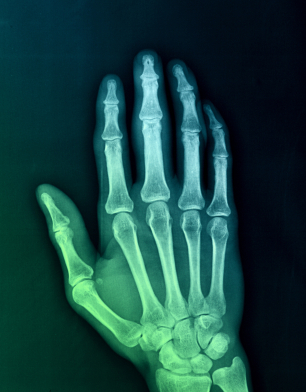

In the third and final segment of neuro.RAPT's three part film series dedicated to Our Hands, Orthopedic Surgeon Dr. Taizoon Baxamusa covers:

1) What is arthritis?

2) What happens when arthritis gets so severe that it interferes with our daily lives?

3) How does the body take attempts to stabilize arthritis?

4) Is there a correlation of x-ray images of arthritis and the severity of the symptoms?

5) What is basilar joint arthritis?

6) How do you treat arthritis?